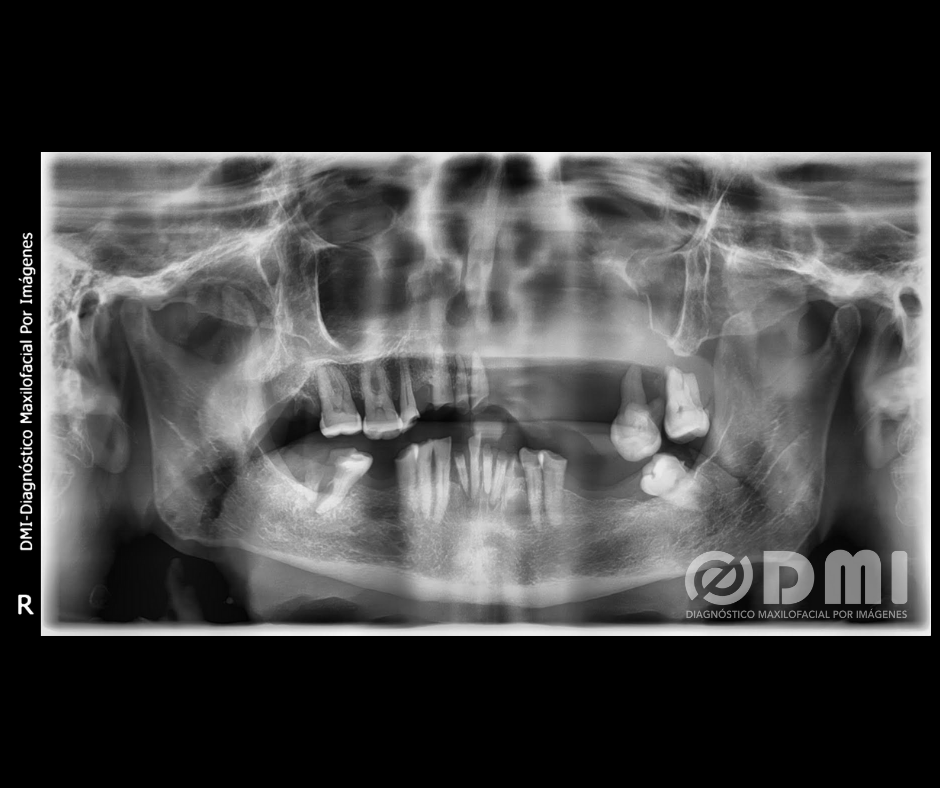

Paciente masculino de 66 años de edad, es remitido a DMI para evaluación mediante tomografía cone beam.

Paciente desdentado parcial superior e inferior; remanentes radiculares con proceso osteolítico periapical. El Od No. 33 presenta imagen radiolúcida; Aspecto de diente flotante de los Od No. 12, 11, 27 y 28. Desplazamiento caudal y reabsorción radicular externa en Od No. 27 y 28. Od No. 47 en posición mesioangular, caries corono radicular que ocasiona fractura vertical. Proceso osteolítico periapical con incremento de la densidad ósea circundante (Osteítis condensante). Reabsorción ósea alveolar generalizada. Presencia de placa calcificada. imagen radiolúcida de forma redondeada, límites definidos y bordes corticalizados. Pérdida de estructura dentaria incisal y oclusal generalizada por atrición. Disminución generalizada de la densidad ósea caracterizada por adelgazamiento de corticales óseas y aumento en el diámetro de los espacios medulares.

Al evaluar el caso mediante tomografía cone beam se evidencia la presencia de lesión osteolítica isodensa ubicada en el maxilar superior, que se extiende desde la tuberosidad maxilar del lado izquierdo hasta el Od No. 15 y desde la cima de reborde alveolar hasta el piso de órbita ipsilateral, de límites difusos, con presencia de imágenes hiperdensas de densidad ósea en su interior, que ocasiona perforación del proceso palatino, piso y paredes lateral y medial de la fosa nasal del lado izquierdo y derecho, piso de seno maxilar y pared medial del lado derecho, septum nasal, paredes anterior, lateral, medial y posterior del seno maxilar izquierdo, con evidente compromiso de los cornetes nasales inferior y medio del lado izquierdo y unidad ostium meatal, con extensión de la masa tumoral hasta las coanas, con compromiso de la vía aérea nasal, fosa pterigomaxilar, proceso cigomático izquierdo y hueso malar ipsilateral. Aspecto de diente flotante de los Od No. 12, 11, 27 y 28. Desplazamiento caudal y reabsorción radicular externa en piezas 27 y 28.

Lesión osteolítica isodensa ubicada en el maxilar superior, de límites difusos, con presencia de imágenes hiperdensas de densidad ósea en su interior, que ocasiona perforación del proceso palatino, piso y paredes lateral y medial de la fosa nasal del lado izquierdo y derecho, piso de seno maxilar y pared medial del lado derecho, septum nasal, paredes anterior, lateral, medial y posterior del seno maxilar izquierdo, con evidente compromiso de los cornetes nasales inferior y medio del lado izquierdo y unidad ostium meatal, con extensión de la masa tumoral hasta las coanas, con compromiso de la vía aérea nasal, fosa pterigo maxilar, proceso cigomático izquierdo y hueso malar ipsilateral. Condiciona aspecto de diente flotante de Od No.12, 11, 27 y 28. Desplazamiento caudal y reabsorción radicular externa en Od No. 27 y 28. Signos tomográficos sugerentes de Neoplasia Maligna. Se recomendó realizar análisis histopatológico.